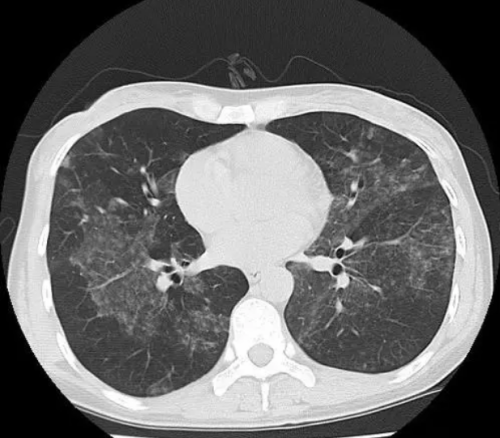

就诊,胸部CT显示双肺弥漫性病变,考虑感染性病变,需要住院诊治。

住院后,在短短2天时间内,袁江的病情以惊人的速度恶化了:反复高烧,体温屡屡超过39℃,伴随剧烈咳嗽,呼吸困难进行性加重,胸部CT复查显示双肺病灶明显增多,呈现“白肺”样改变。由于病情危重,3月17日,袁江由当地立博体育